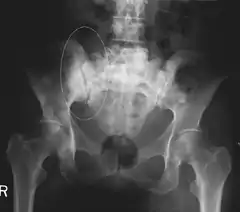

Skeletal Radiography

A plain film x-ray of the entire body can identify bone metastasis, however, the sclerotic or osteolytic lesions must be at least 1 cm in diameter.[13] A combination of X-ray, CT and MRI scans provides optimal structural information of the metastases.